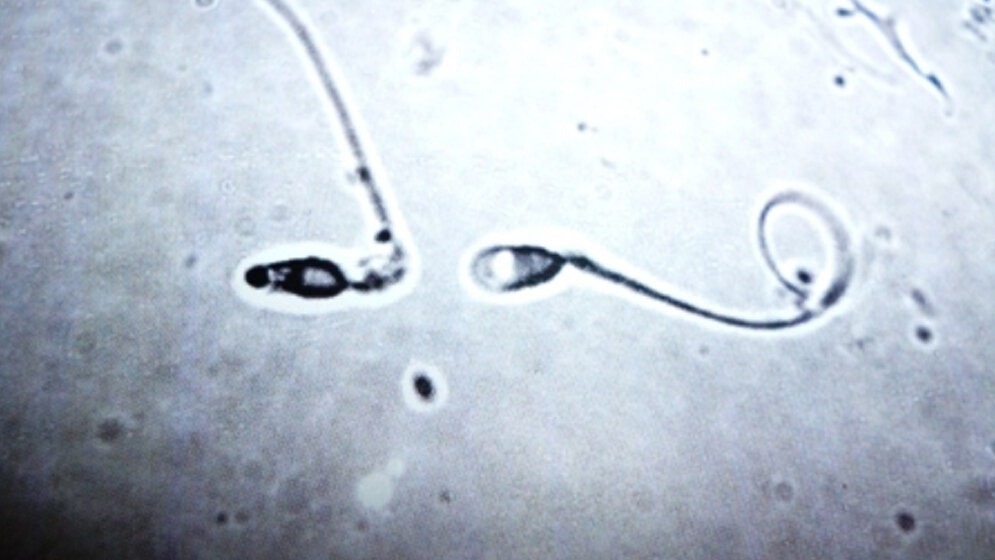

Die Wissenschaftler hatten zuvor bewiesen, dass männliche Unfruchtbarkeit genetisch erreicht werden kann, indem man zeitgleich zwei Proteine (α1A-Adrenozeptor and P2X1-Purinozeptor) hemmt, die den Spermientransport auslösen, ohne aber die langfristige Funktionsfähigkeit der Spermien bzw. die sexuelle und allgemeine Gesundheit zu gefährden. Die Spermien sind also weiterhin vorhanden, erhalten nur nicht das chemische Signal, sich zu bewegen. Es gibt bereits ein weit verbreitetes Medikament, das eines der beiden Proteine erfolgreich hemmt, nun wollen die Wissenschaftler einen Weg finden, auch das zweite Protein zu blockieren.

„Unser Ziel ist es nicht, die Spermienproduktion zu hemmen, sondern den Spermientransport zu unterbinden.“ Weitere genetische Studien hätten bewiesen, dass die Spermien bei Medikamenteneinnahme langfristig gesund und funktionsfähig bleiben, da nur der Transport blockiert wird. Auch die Libido und die sexuelle Aktivität seien unbeeinflusst, so Dr Ventura.